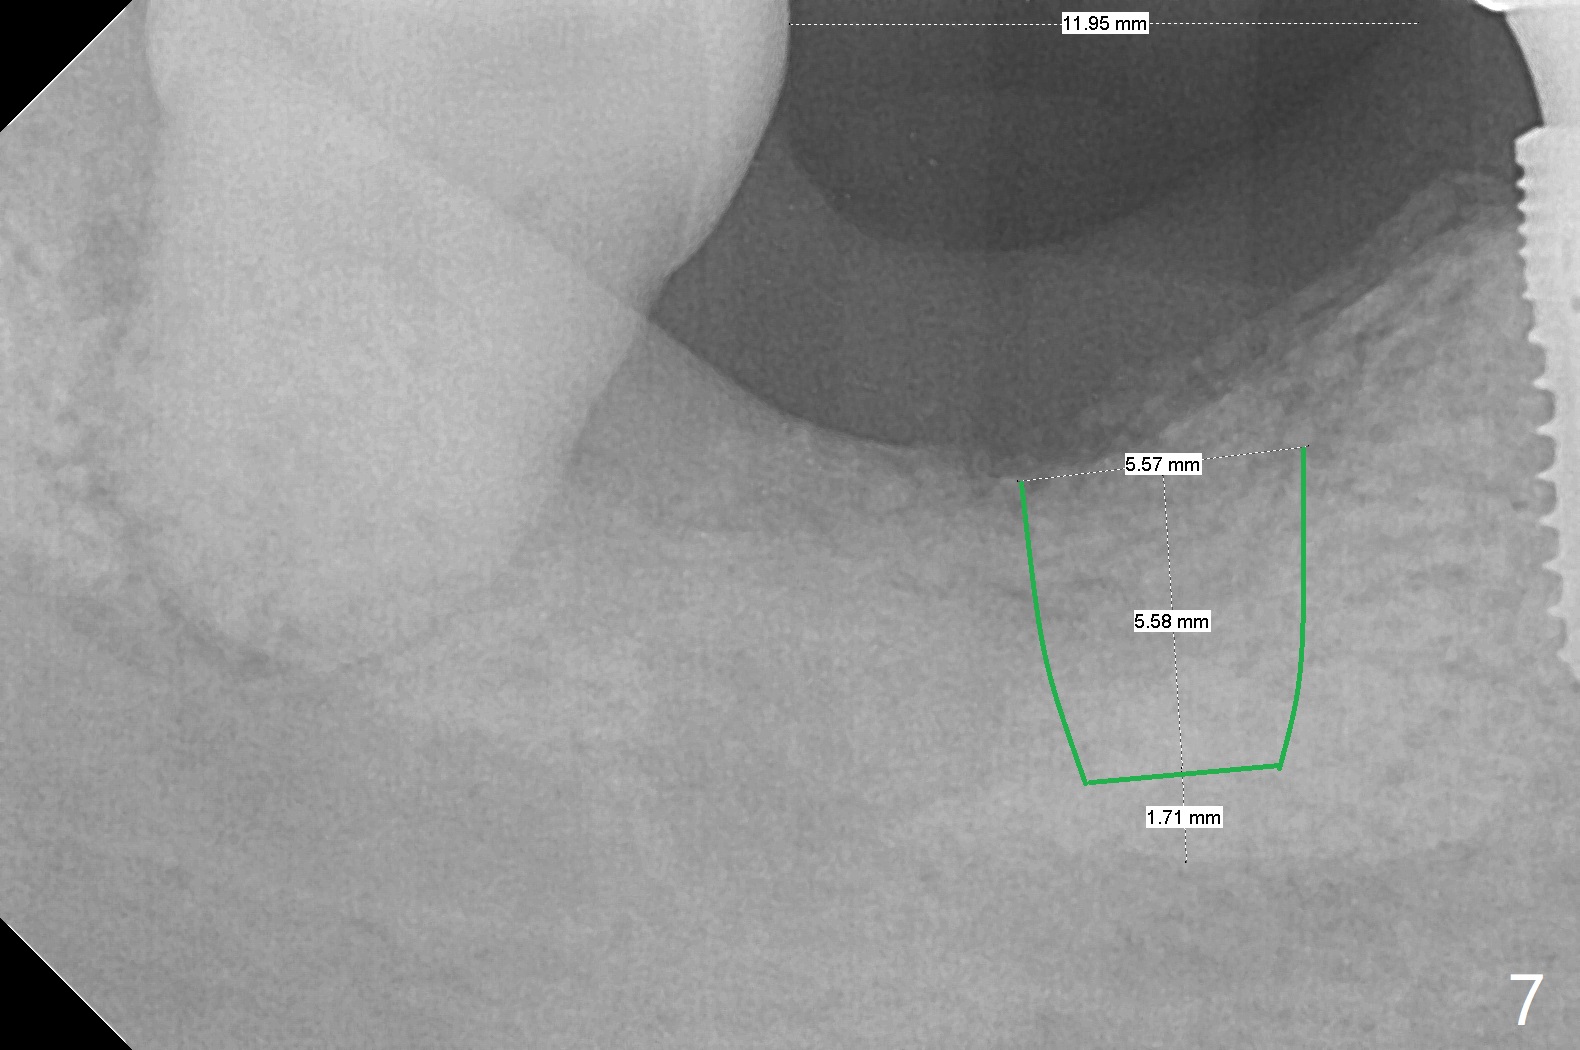

Although the bony socket is shallow, the soft tissue one remains deep at #31 with gingival recession (Fig.1 *). The deep soft tissue socket with hemorrhage after extraction presents difficulty in debridement of granulation tissue apically. After placement of allograft (Fig.3 *) and overlying collagen membrane (Fig.2 C), the socket is closed with 4-0 Chromic gut suture. In fact, there is ~ 2 mm granulation tissue left (Fig.4 red (yellow line: upper border of the Inferior Alveolar Canal)). To reduce socket shrinkage, the tooth #32 is not extracted. The collagen membrane has lost 1 week postop (Fig.5). More sutures should have been used, preferably using Human Amnion Chorion Allgraft as a membrane. The latter promotes wound healing. The bone graft also seems to have lost in 8.5 months (Fig.6). A short implant will be placed mesially and obliquely (Fig.7).